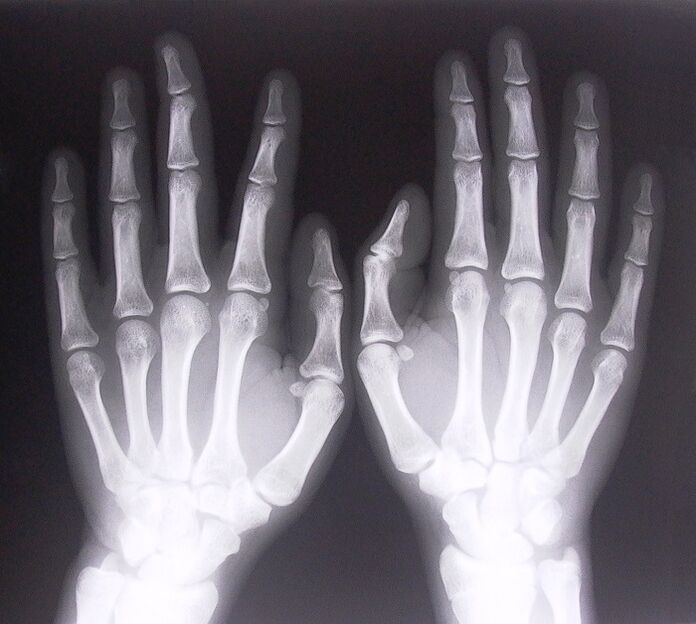

- Fai delle radiografie.

- Legamentite stenosante. Per identificare la causa della malattia, è necessario sottoporsi a una radiografia. I sintomi sono tipici: movimento doloroso della mano, avvolgimento del palmo chiuso. Inoltre, durante l'estensione, di solito si sentono dei clic.